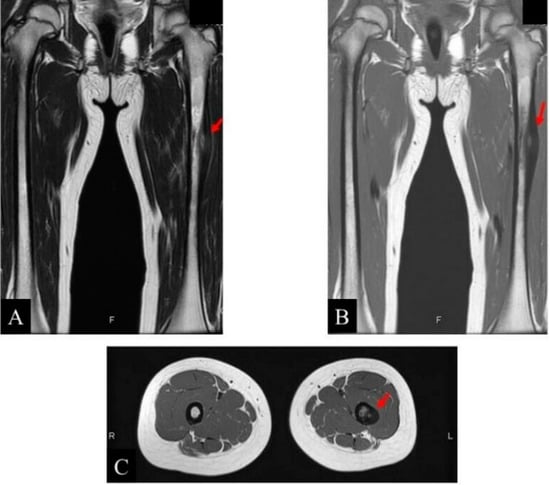

- Clinical and radiological evaluation of the osteoid osteoma.